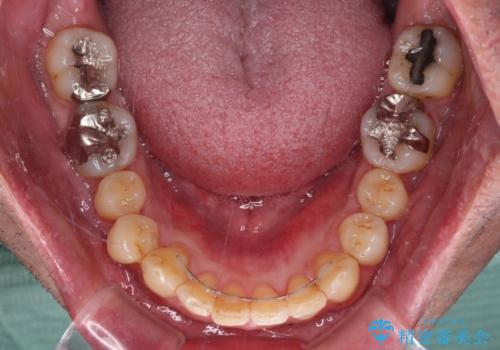

- 外に飛び出した側方の歯と、前歯のデコボコを気にして来院された患者様です。

IPR(歯と歯の間を削る)によってデコボコが解消するように設計し、インビザラインにより治療を行うこととしました。

治療途中で1年半以上通院されない時期があったため、後戻りが生じたことで治療期間が長くなってしまいました。

親知らずを抜去したことで、下顎のデコボコがきれいに解消されました。